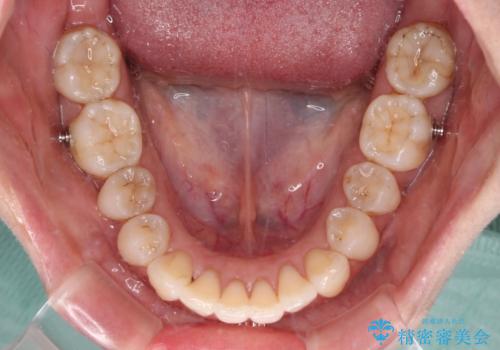

補助装置を用いて奥歯の咬み合わせを事前に改善 インビザラインによる矯正治療

歯列としてはインビザラインでもワイヤー矯正でも対応できるものでしたが、奥歯の咬み合わせを見た時に上顎がやや前方にあり、インビザライン単独では時間のかかってしまう可能性があるため、補助装置を治療当初に使用することで、インビザラインによる治療をスムーズに行えるように計画しました。

インビザラインは得意・不得意の差がはっきりとしているため、補助装置やワイヤー装置などをうまく活用することで、治療期間を短縮するとともに、より理想的な仕上がりを達成することができます。